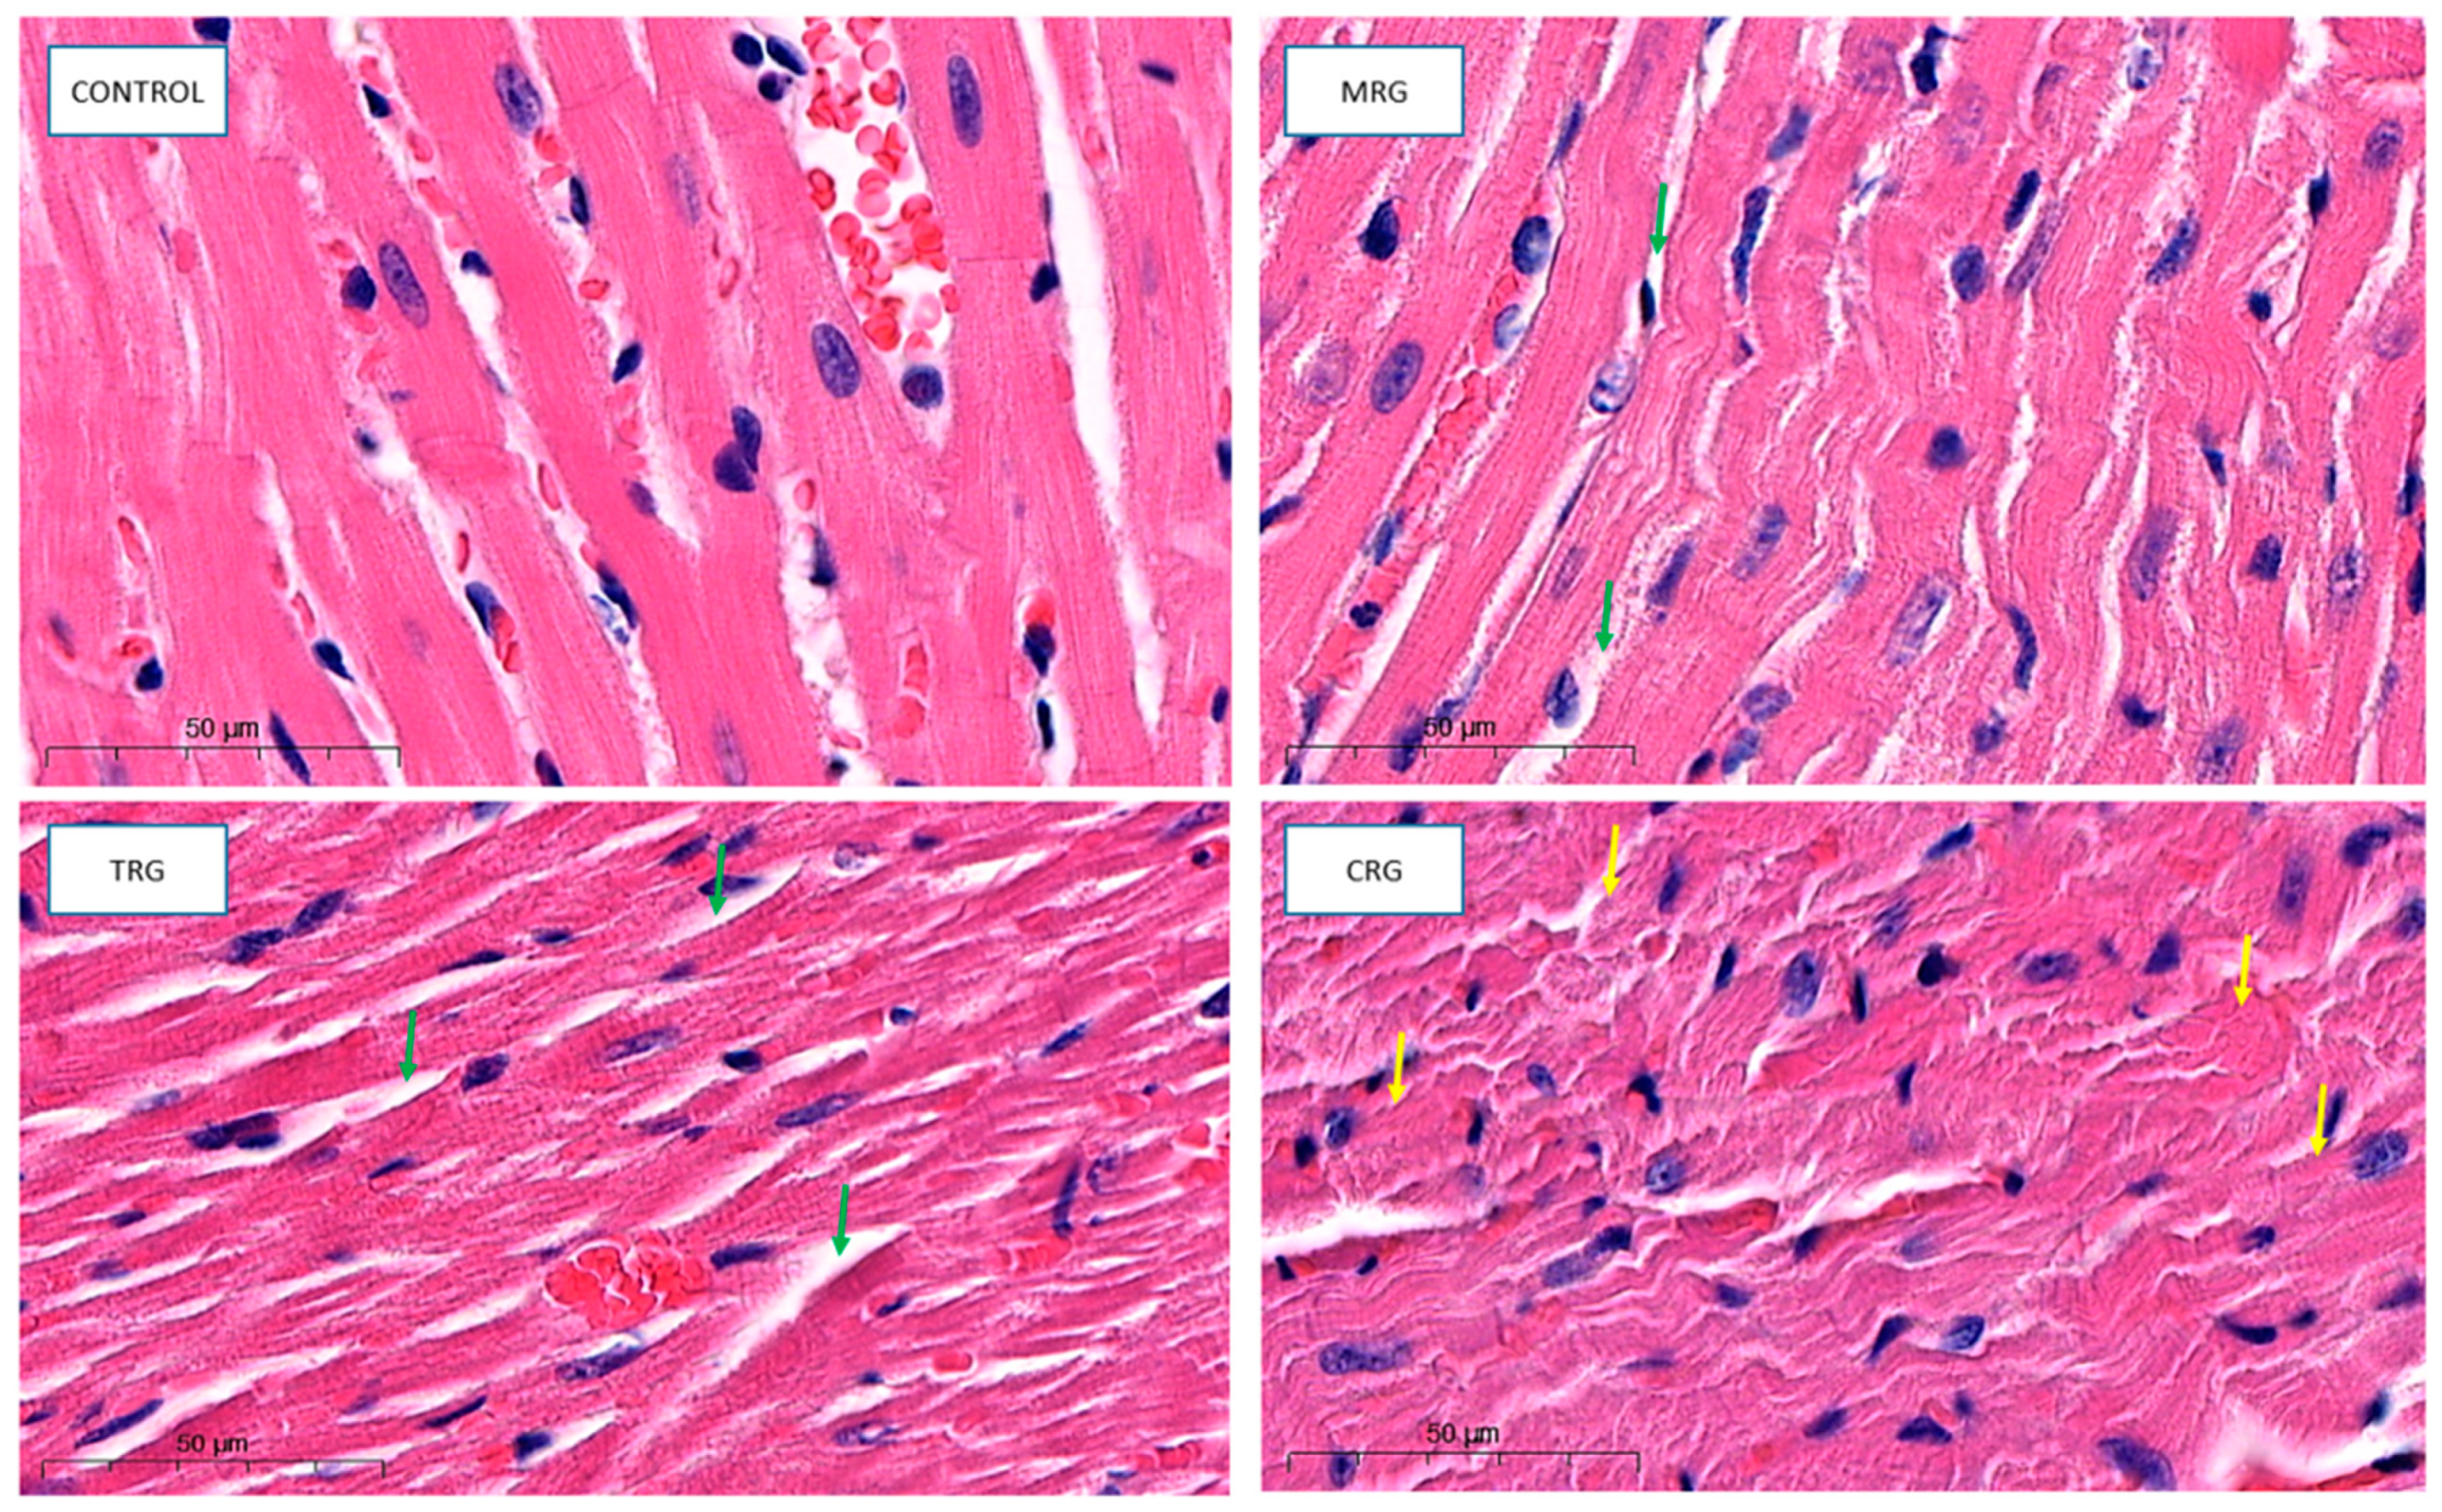

2.2. Morphology

3.1. Morphology